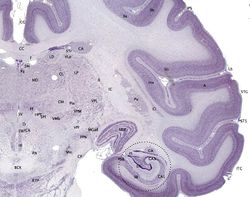

القشرة المخية هي الطبقة الخارجية تظهر باللون البنفسجي الداكن. | ||

القشرة المخية إنگليزية: Cerebral cortex هي الطبقة السطحية من نصف كرة المخ لدى الثديات. والقشرة المخية لدى الأنسان تتكون من المادة الرمادية والتي يتألف معضمها من العصبونات الهرمية المرتبة في 6 طبقات فيما يعرف القشرة الجديدة. وهذا الترتيب هو ما يجعل مخ الأنسان معقد وقادر على الفهم والاستيعاب. كما يتيح هذا الترتيب إلى تقسيم المهام المختلفة إلى مختلف مناطق القشرة والتي سيتم ذكرها لاحقاً. كما أن القشرة المخية تتكون من الأخاديد والتلافيف التي تساعد على زيادة مساحة القشرة بشكل كبير (ثلثي القشرة تقع في الأخاديد). كما تستعمل الأخاديد - تشريحياً - في تقسيم المخ إلى مناطق وظيفية، بحيث تكون كل منطقة مسؤولة عن وظيفة محددة مما يزيد التخصيص والدقة في عمل الدماغ البشري. على الرغم من كمية المهام التي تؤديها القشرة فسماكتها تتراوح بين ٢-4 مم.